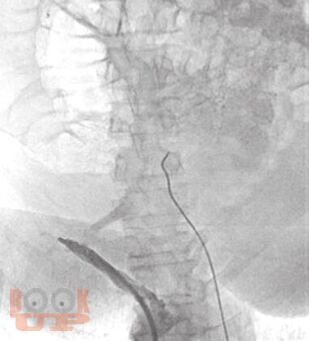

В монографии представлены алгоритмы периоперационного ведения пациентов с циррозом печени, стандарты диагностики, предоперационной подготовки и послеоперационной реабилитации. Рассмотрены принципы формирования и тактика ведения листа ожидания трансплантации печени, а также технология проведения хирургического вмешательства.

Проанализированы выявленные ошибки и предложен междисциплинарный подход в тактике периоперационного ведения пациентов с участием хирургов, гастроэнтерологов, эндоскопистов, эндоваскулярных хирургов.